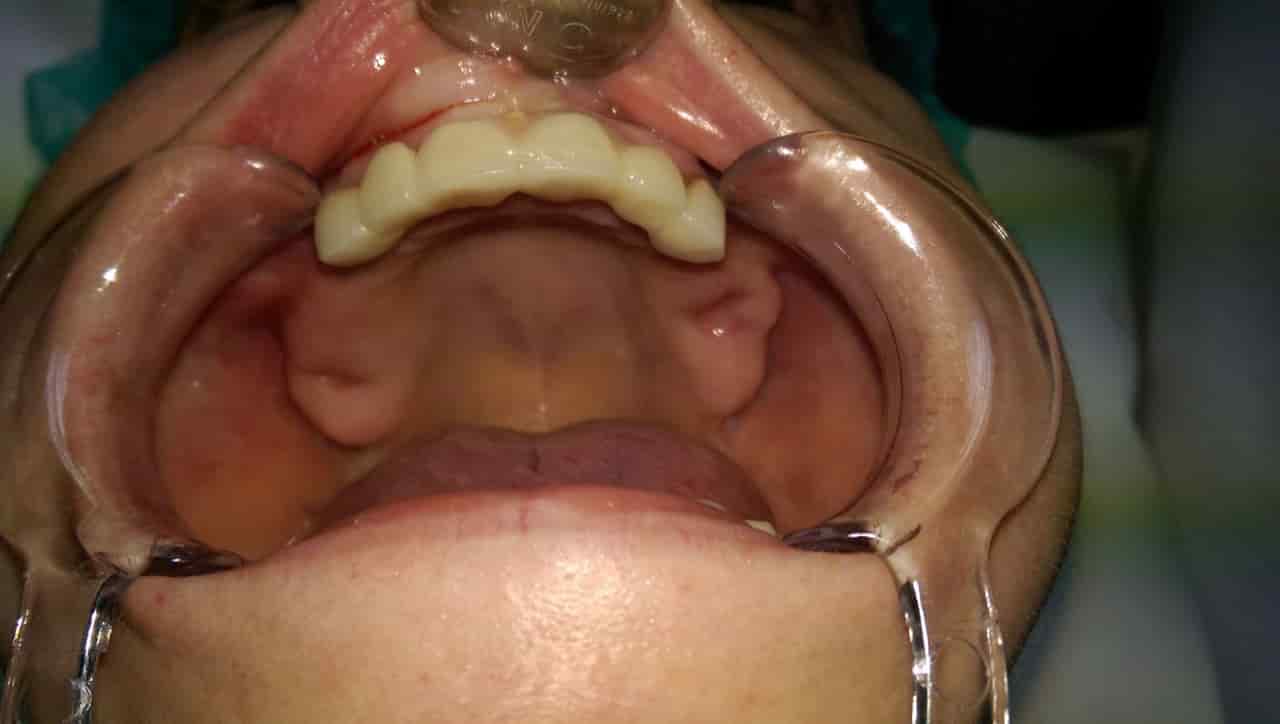

Az ínysorvadás egy alattomos betegség, ami egyre több embert érint a modern kor társadalmában. Gyakran a fogápolás elhanyagolása a kialakulás oka, máskor pedig a nem megfelelő élelmiszer fogyasztásában keresendő a hiba. Szerencsés helyzet, ha időben észbe kapunk és megelőzzük a komolyabb fogvesztést, de számos esetben már nincs mit tenni. Ilyenkor választható alternatíva az implantátum Budapest behelyezése az eredeti rágóeszközök helyére.

Ez a metódus pontosan olyan jellegű pótlást kínál, amivel egyértelműen meg leszünk elégedve. Mivel nem kivehető, így nagymértékben hasonlít az elveszített fogakhoz. Az implantátum Budapest további előnye, hogy gyorsan elkészül. Bárki jelentkezhet a kezelésre.

Amíg más esetekben a cukorbetegség, dohányzás, csontritkulás kizáró tényezők, addig az itt nem jelent gondot. A dentalcenterkelemen.hu felületen minden részletre fény derül. Profi szakemberek várják hívásunkat és az implantátum Budapest beillesztése hamarosan kezdetét veheti. Rövid gyógyulási idővel lehet számolni és a minimális fájdalomtól sem érdemes megijedni.